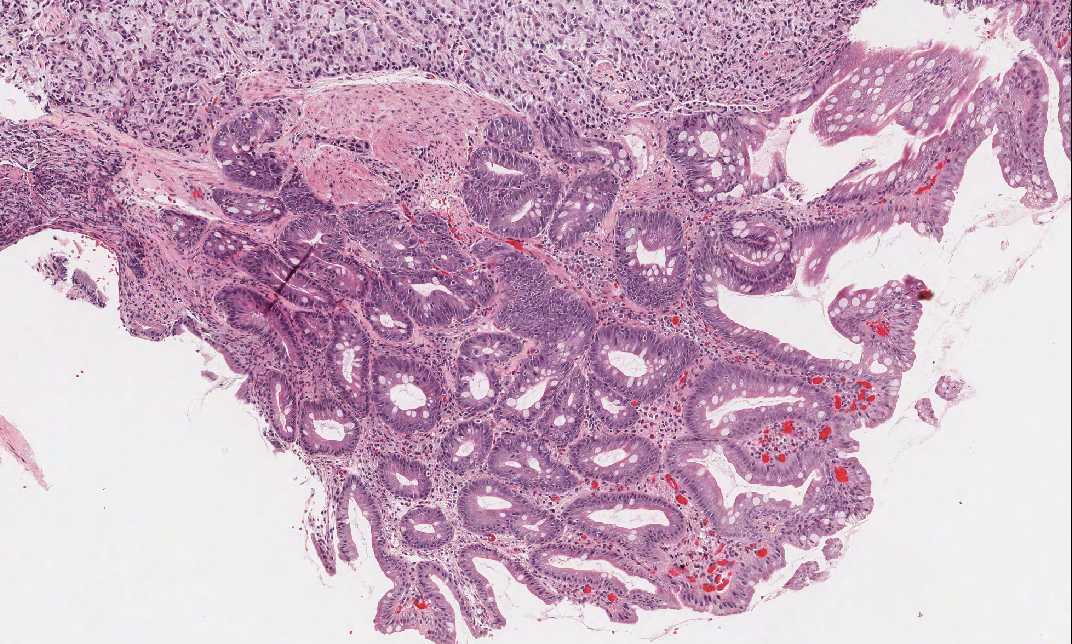

Area 1: This is the area with gastric mucosa fragments. Note that intestinal metaplasia is present in some of the fragments.

• There are residual gastric mucosa with intestinal metaplasia which helps to identify this specimen as stomach (Area 1). These are areas with atrophic gastritis and intestinal metaplasia.